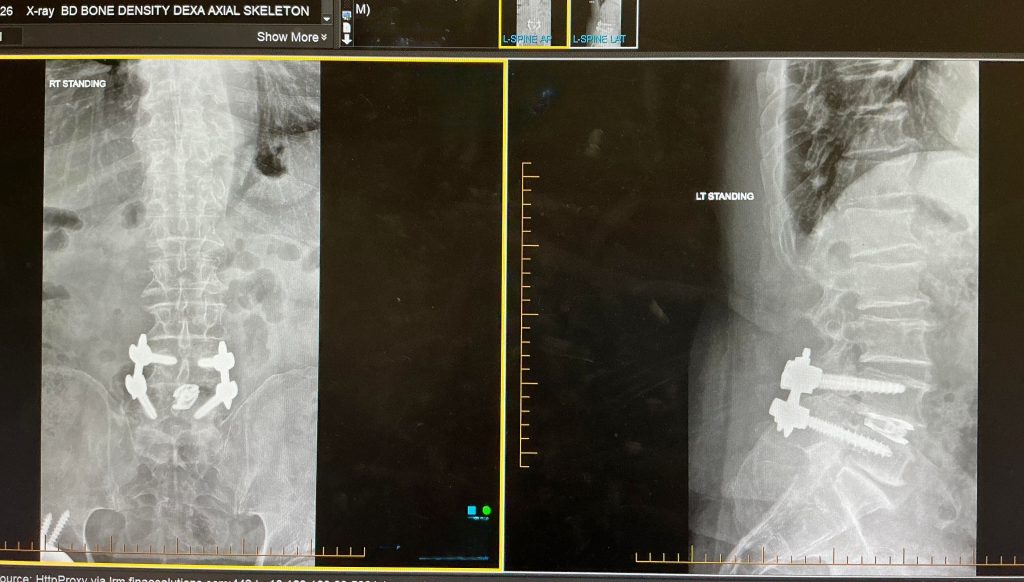

Anabolic is a unique fitness term that provides a process to naturally build muscle, repair tissue, and even restore a youthful appearance even for those of us over the age of 60. Let me state that I am just now getting back into my BAJA Fitness routine after my back surgery in February of 2026. By June of 2026, I hope to be released to perform all of the BAJA Fitness elements.

Standing Hamstring Stretch lengthens the backs of the legs, reducing lower-back tension and enhancing stride length. In February, I had back surgery and Standing Hamstring Stretch was very beneficial after 8- weeks of rehabbing.

Tabletop Knee Lift Crunch targets the deep abdominal muscles, improving spinal stability and core endurance. The Tabletop Knee Lift Crunch is more effective and less strain on the lumbar area. My Neurospin surgeon suggests that the Tabletop Knee Lift Crunch in lieu of typical sit-ups to reduce stress on the lumbar area.